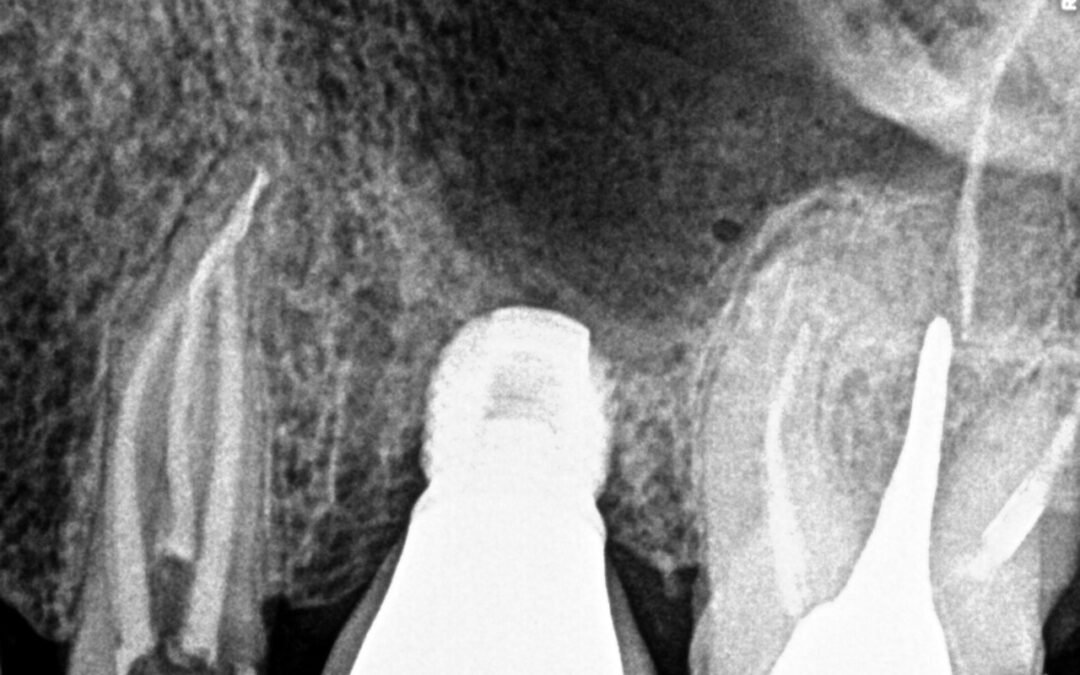

Remoção de broca gates fraturada dentro do canal

Remoção de broca gates fraturada dentro do canal De acordo com a imagem abaixo foi feita a remoção de um fragmento fraturado dentro do canal utilizando pontas especificas de ultrassom.   Pesquisar por: Posts recentes Remoção de cone de prata molar superior...